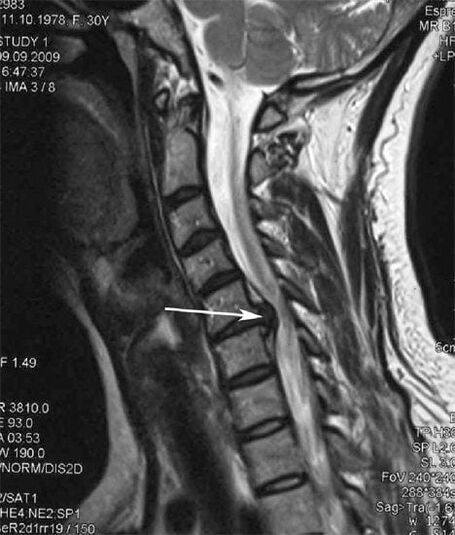

Στα αρχικά στάδια, η οστεοχόνδρωση ανιχνεύεται με μαγνητική τομογραφία. Αργότερα, η παθολογία μπορεί να διαγνωστεί χρησιμοποιώντας ακτινογραφία. Στις ακτινογραφίες της αυχενικής μοίρας της σπονδυλικής στήλης, η μείωση της απόστασης μεταξύ των σπονδύλων, οι παθολογικές αλλαγές στις αρθρώσεις της όψης και η οστεοφυτία γίνονται αισθητές.

Πολλοί άνθρωποι παραπονιούνται ότι δεν μπορούν να γυρίσουν τον λαιμό τους λόγω έντονου πόνου που εμφανίζεται μετά από ξαφνική άρση κάτι βαρύ. Αυτό το φαινόμενο υποδηλώνει το σχηματισμό κήλης δίσκου. Η αιτία του πόνου στην πλάτη, τον αυχένα και το άνω άκρο είναι το τσίμπημα μιας από τις νευρικές ρίζες που αναδύονται από το νωτιαίο μυελό.